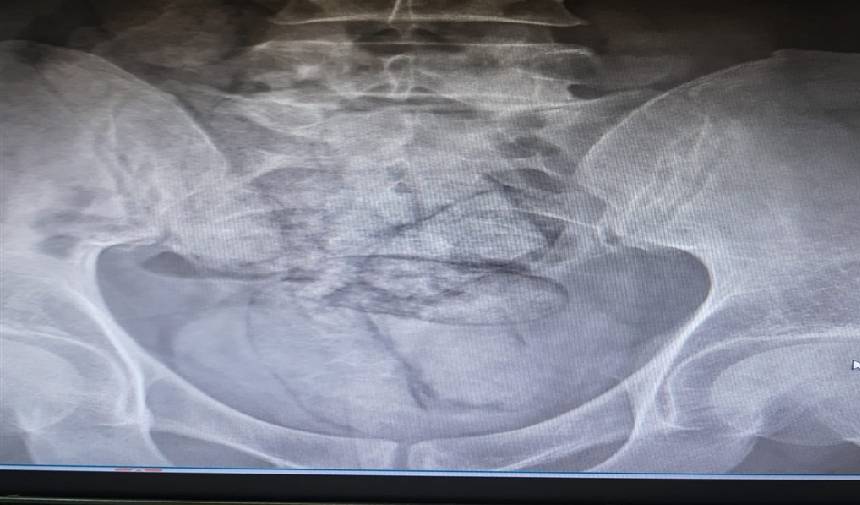

Artvin Devlet Hastanesi’nde tomografisi çekilen şüphelinin bağırsaklarında 10 paket halinde uyuşturucu madde taşıdığı belirlendi. Şüphelinin hayati tehlike oluşturabilecek şekilde sakladığı paketler, cerrahi müdahaleyle çıkarıldı. İncelemede paketlerin içinde toplam 350 gram metamfetamin olduğu tespit edildi.